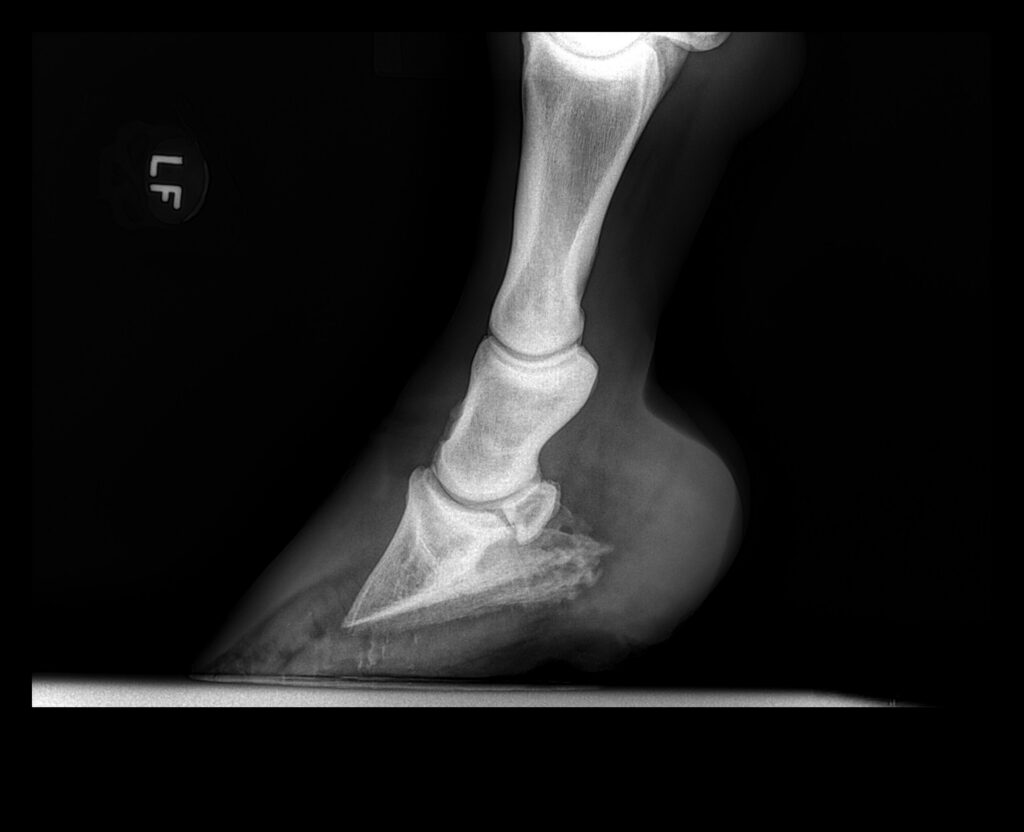

Understanding the disease starts with looking at the unique anatomy of the horse’s foot. The coffin bone is held within the hoof capsule by a series of laminae, which are finger-like projections of highly vascular connective tissue. The laminae inside the hoof wall are woven into the corresponding laminae on the surface of the coffin bone, forming a tight “Velcro-like” connection between bone and hoof. When a horse develops laminitis, inflammation interrupts blood flow to the laminae, which compromises the attachment between the coffin bone and hoof. The inflamed laminae become weak and may detach, leading to rotation or sinking of the coffin bone within the hoof capsule. Laminitis with coffin bone rotation is often referred to as founder.

Digital pulses, which are felt along the fetlocks and pasterns, will be increased in both rate and character, secondary to the inflammation within the feet. Horses are often reactive to hoof testers at the point of the frog, where the coffin bone is closest to the ground. A veterinary exam will likely involve radiographs of the feet, to see if there has been any rotation of the coffin bone. A venogram may be performed to evaluate the integrity of the blood flow within the foot.